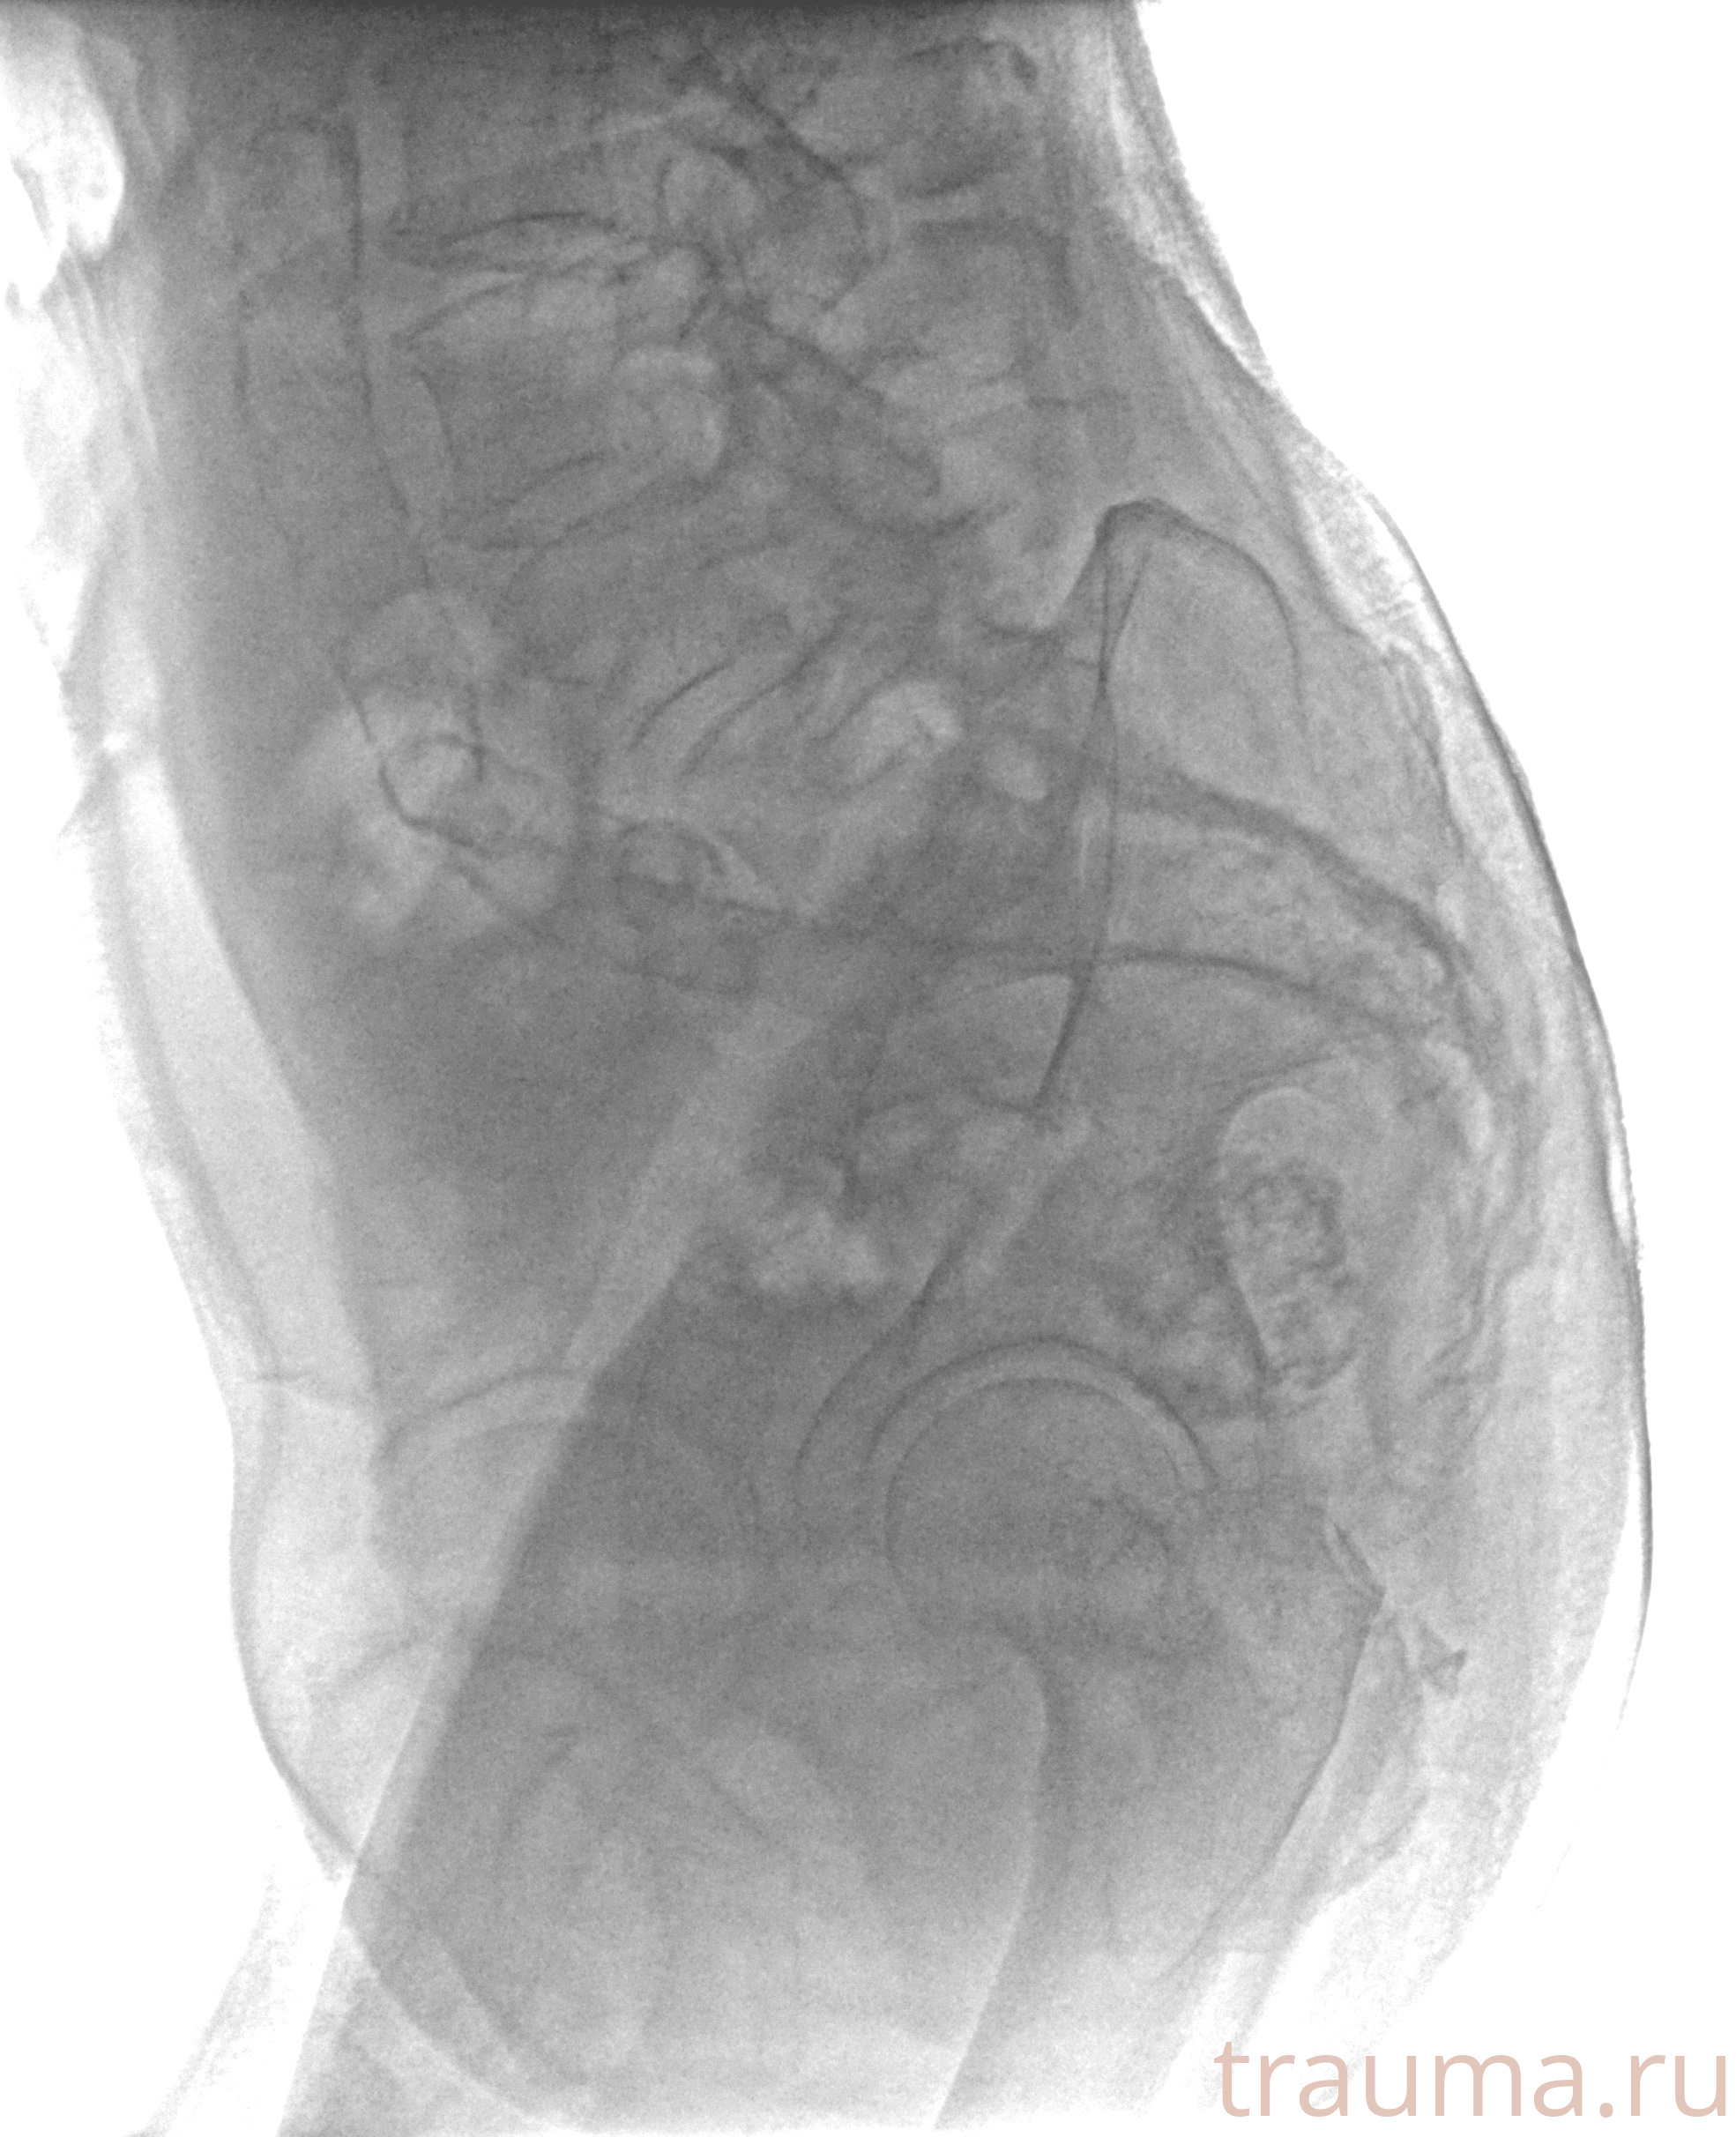

Рентгенограммы

Рентген на дому: по вашему адресу приезжает врач-рентгенолог, травматолог-ортопед с мобильным рентгеновским аппаратом, проводит диагностику травмы или заболевания, делает необходимые рентгенограммы, дает рекомендации по дальнейшему лечению. Получить качественные снимки в домашних условиях возможно благодаря уникальной методике, разработанной МосРентген Центром для института  Склифосовского